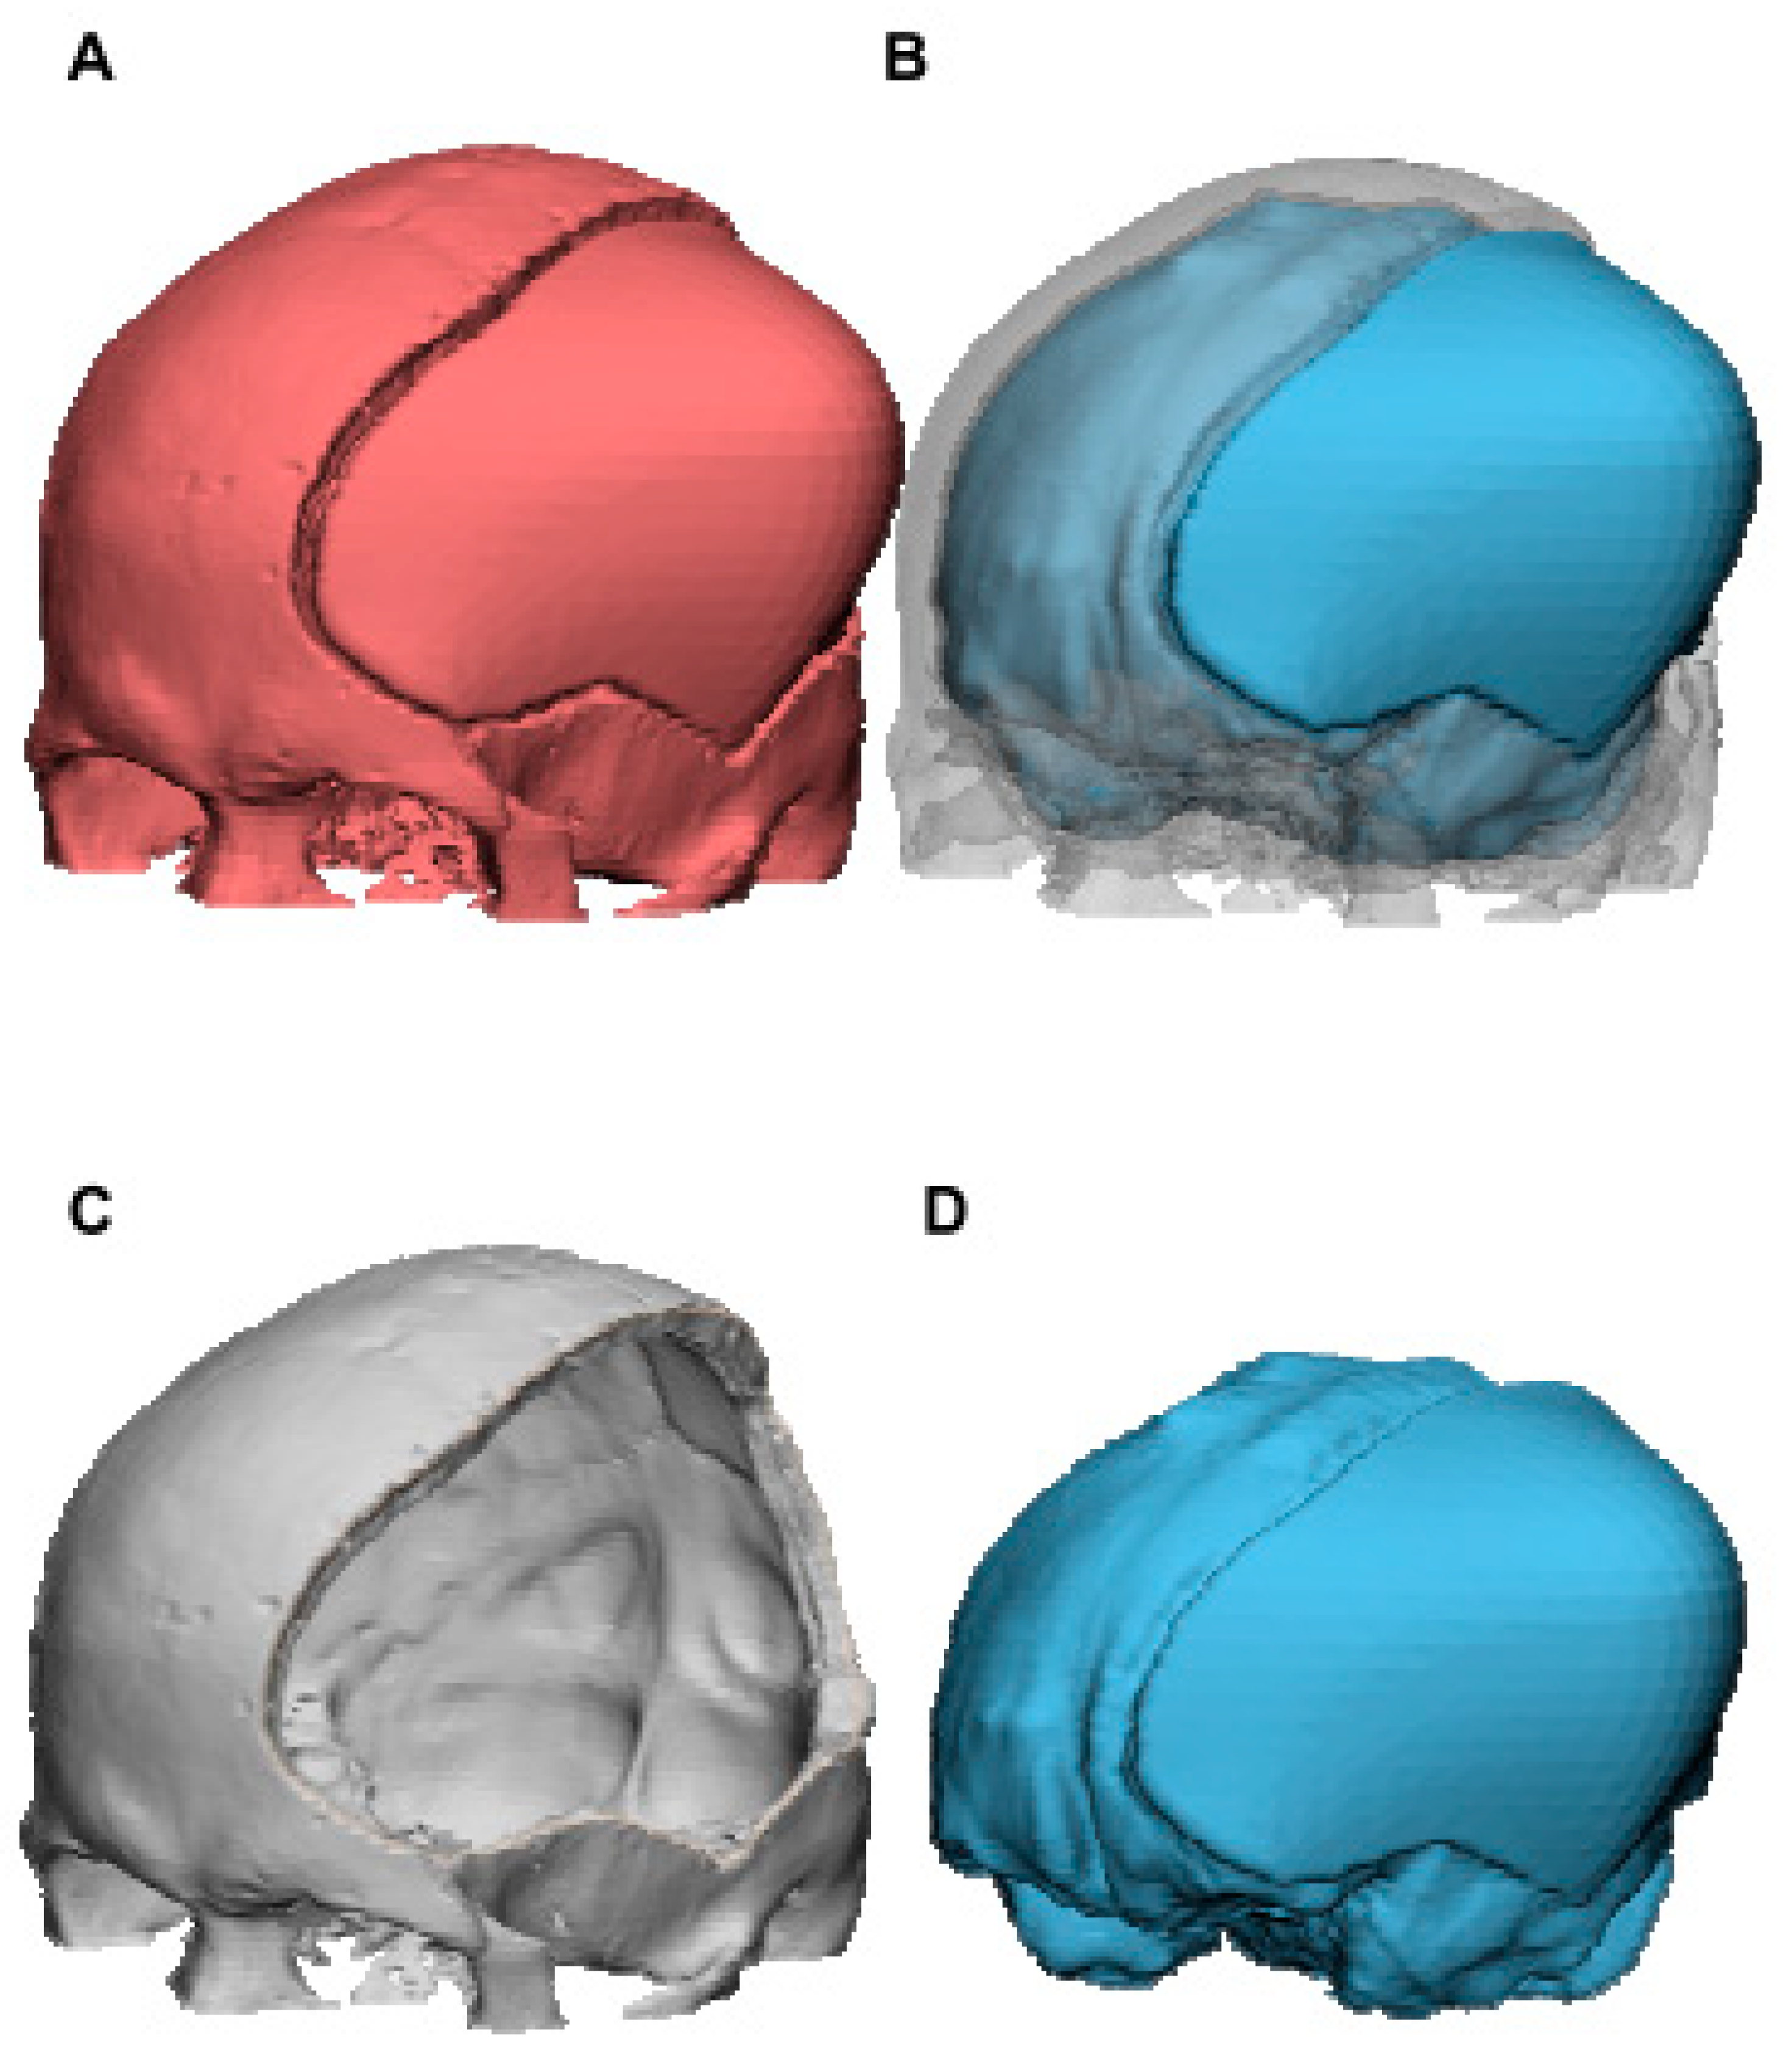

The following calculation was performed to obtain the brain tissue volume for the 15 subjects: volumes from the whole CAD reconstruction (red color, Figure 4A), which corresponded to the two-color mixing model of Figure 4B (skull bone in gray color plus brain tissue in blue color), minus those of skull bone (indicated in gray color, Figure 4C), are equal to the brain tissue volume (indicated in blue color, Figure 4D). Brain tissue volume and volume-increasing rate were calculated for each outward expansion in each model.

Figure 4. The 3D CAD model for calculation of brain tissue volume of case 3 using Materialise 3-matic. Brain tissue volume (D) was obtained by subtracting those of skull bone (C) from the whole CAD reconstruction (A). Volume of (B), which corresponded to (A), is equal to the sum of (C,D).